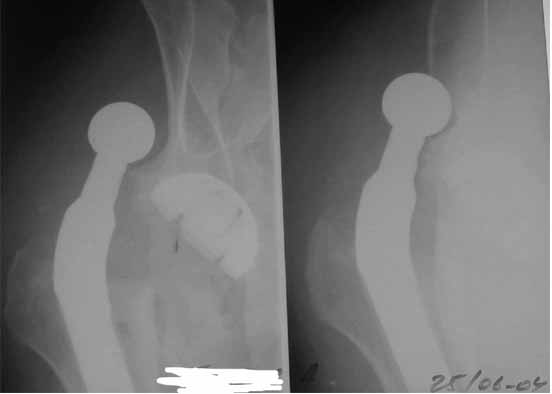

Во вложении - рентгенограммы после вывиха и после вправления.

Если же вывих произошел по причине неправильной ориентации ножки (чего по снимкам нельзя исключить), то конечно же он будет повторяться и

постельный режим тут ничем не поможет. Необходима ревизия с заменой неправильно имплантированного компонента и тщательным восстановлением капсулы и мышц в зоне сустава...

1. Ревизия безотлагательно.

2. Вывихивание протеза, снятие головки

3. Экстракция ножки до уровня, когда ее диаметр станет меньше, чем

диаметр посадочного места в канале бедренной кости.

4. Внутренняя ротация ножки на 1-2 насечки (они есть на ножке Вагнера и довольно хорошо позволяют ориентироваться - это около 10-20 град), т.к. проблема именно в том, что ножка установлена с

ошибочно заданным углом антеверсии и, скорее всего, с избыточным удлинением - именно это мы и увидим на передне-задней рентгенограмме(!) таза.

Консультировать вывихи по рентгенограммам, не зная хода операции, дело не очень благодарное. Я думаю, что с датой операции Вы ошиблись и это был 2004 год? Тем не менее. Настораживают два фактора. Первое - не видно большого вертела. Если с мышцами обошлись грубо и их отсекли, то это очень грустно и нужна "связанная" пара, т.н. "constrain cup". Смущает хорошо прослеживаемый малый вертел и небольшая ретроверсия чашки. Возможно это (избыточная ретроверсия ножки и чашки) могло послужить причиной вывиха. Обычно гипсовая повязка после операции не накладывается, значит, были глубокие сомнения у оперировавшего хирурга. В этом случае - ревизия с перестановкой как минимум - ножки, а как максимум - обоих компонентов.